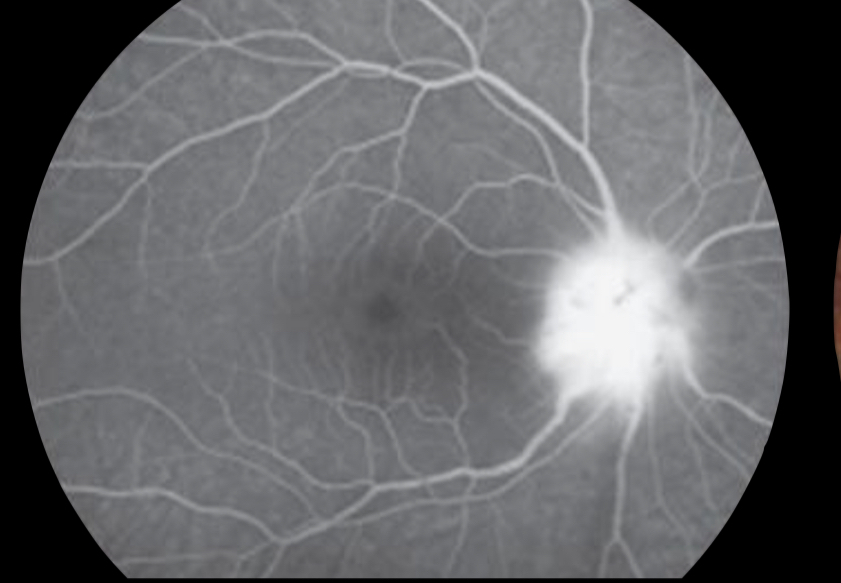

Quais os achados no exame de angiofluoresceinografia de um paciente com neurorretinite?

Extravasamento de contraste proveniente do nervo óptico (nervo quente)